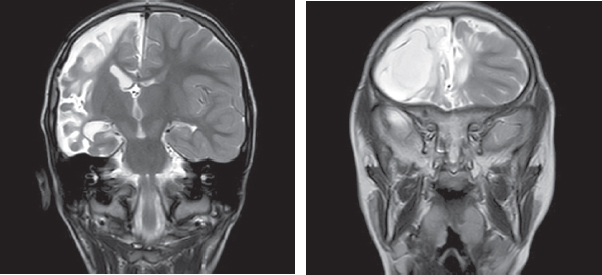

The relevance of studying the consequences of hemorrhagic strokes in young children is due to the frequency of cerebrovascular pathology, the formation of persistent neurological deficits, including post-stroke epilepsy, and high mortality. It is known that hemorrhages are diagnosed in the first 28 days of life in 6-7 out of 100,000 infants, in children from the 28th day of life to 18 years of age from 0.7 to 5.1 cases per 100 thousand children. Mortality in hemorrhagic and ischemic strokes in children ranges from 7 to 28%. Epileptic seizures of the acute and acute period of stroke are prognostically unfavorable factors of the course of the disease. The article presents brief literature data on the etiology and localization of hemorrhagic strokes, their role in the formation of pharmacoresistant epilepsy. Special attention is paid to the role of late hemorrhagic disease of newborns, accompanied by intracranial hemorrhages, in the formation of structural epilepsy in the future. The paper describes own clinical observations of 25 patients suffering from epilepsy after a hemorrhagic stroke with a description of the clinical picture, features of paroxysmal states and their therapy, neuroimaging data, electroencephalographic phenomena. A clinical example is presented in which the clinical, anamnestic, electrophysiological data of a patient with pharmacoresistant epilepsy developed as a result of a hemorrhagic stroke on the background of late hemorrhagic disease of newborns are considered.

Structural epilepsy in children, formed after a hemorrhagic stroke, is accompanied by significant multi-regional damage, pronounced neurological deficit and is characterized by a pharmacoresistant course.